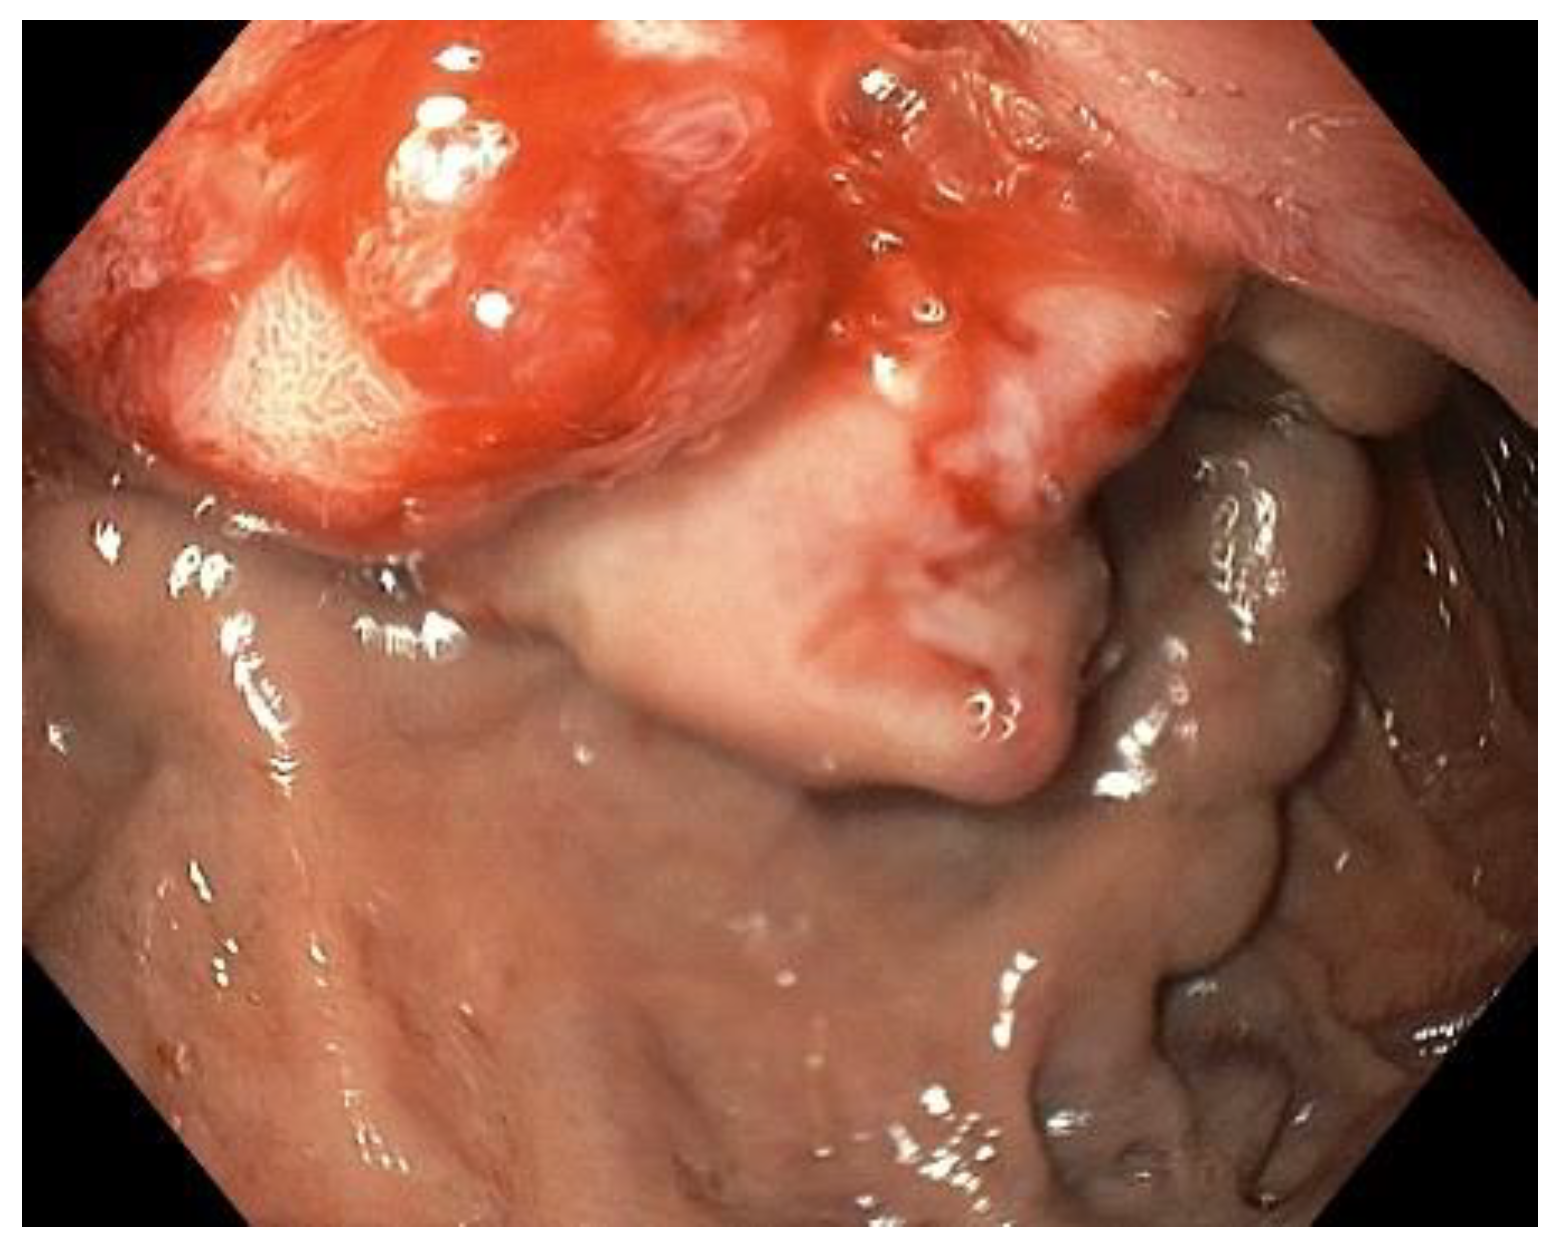

2. Case Description